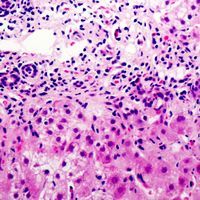

Supportive validation

- Submitted by

- GeneTex (provider)

- Main image

- Experimental details

- Immunohistochemical analysis of Cystatin E/M staining in human liver cancer formalin fixed paraffin embedded tissue section. The section was pre-treated using heat mediated antigen retrieval with sodium citrate buffer (pH 6.0). The section was then incubated with the antibody at room temperature and detected using an HRP conjugad compact polymer system. DAB was used as the chromogen. The section was then counterstained with haematoxylin and mounted with DPX.